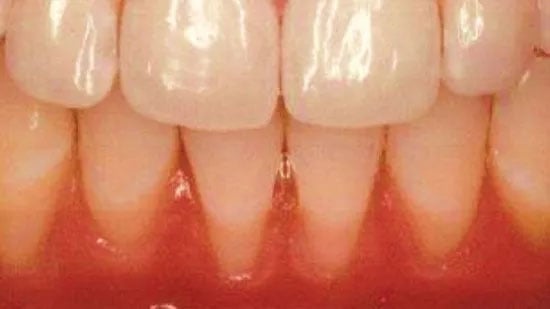

- See below for many before and after possibilities.

Gum recession can occur for a variety of reasons, but periodontal disease is the leading cause. When bacteria invade the gums and bone that support the teeth, these structures will recede and deteriorate. The tooth roots become more visible and the smile takes on a new appearance. Gaps, spaces, abnormally large teeth, and other imperfections can make the smile look less attractive.

Pinhole Case Study

Before & After Results